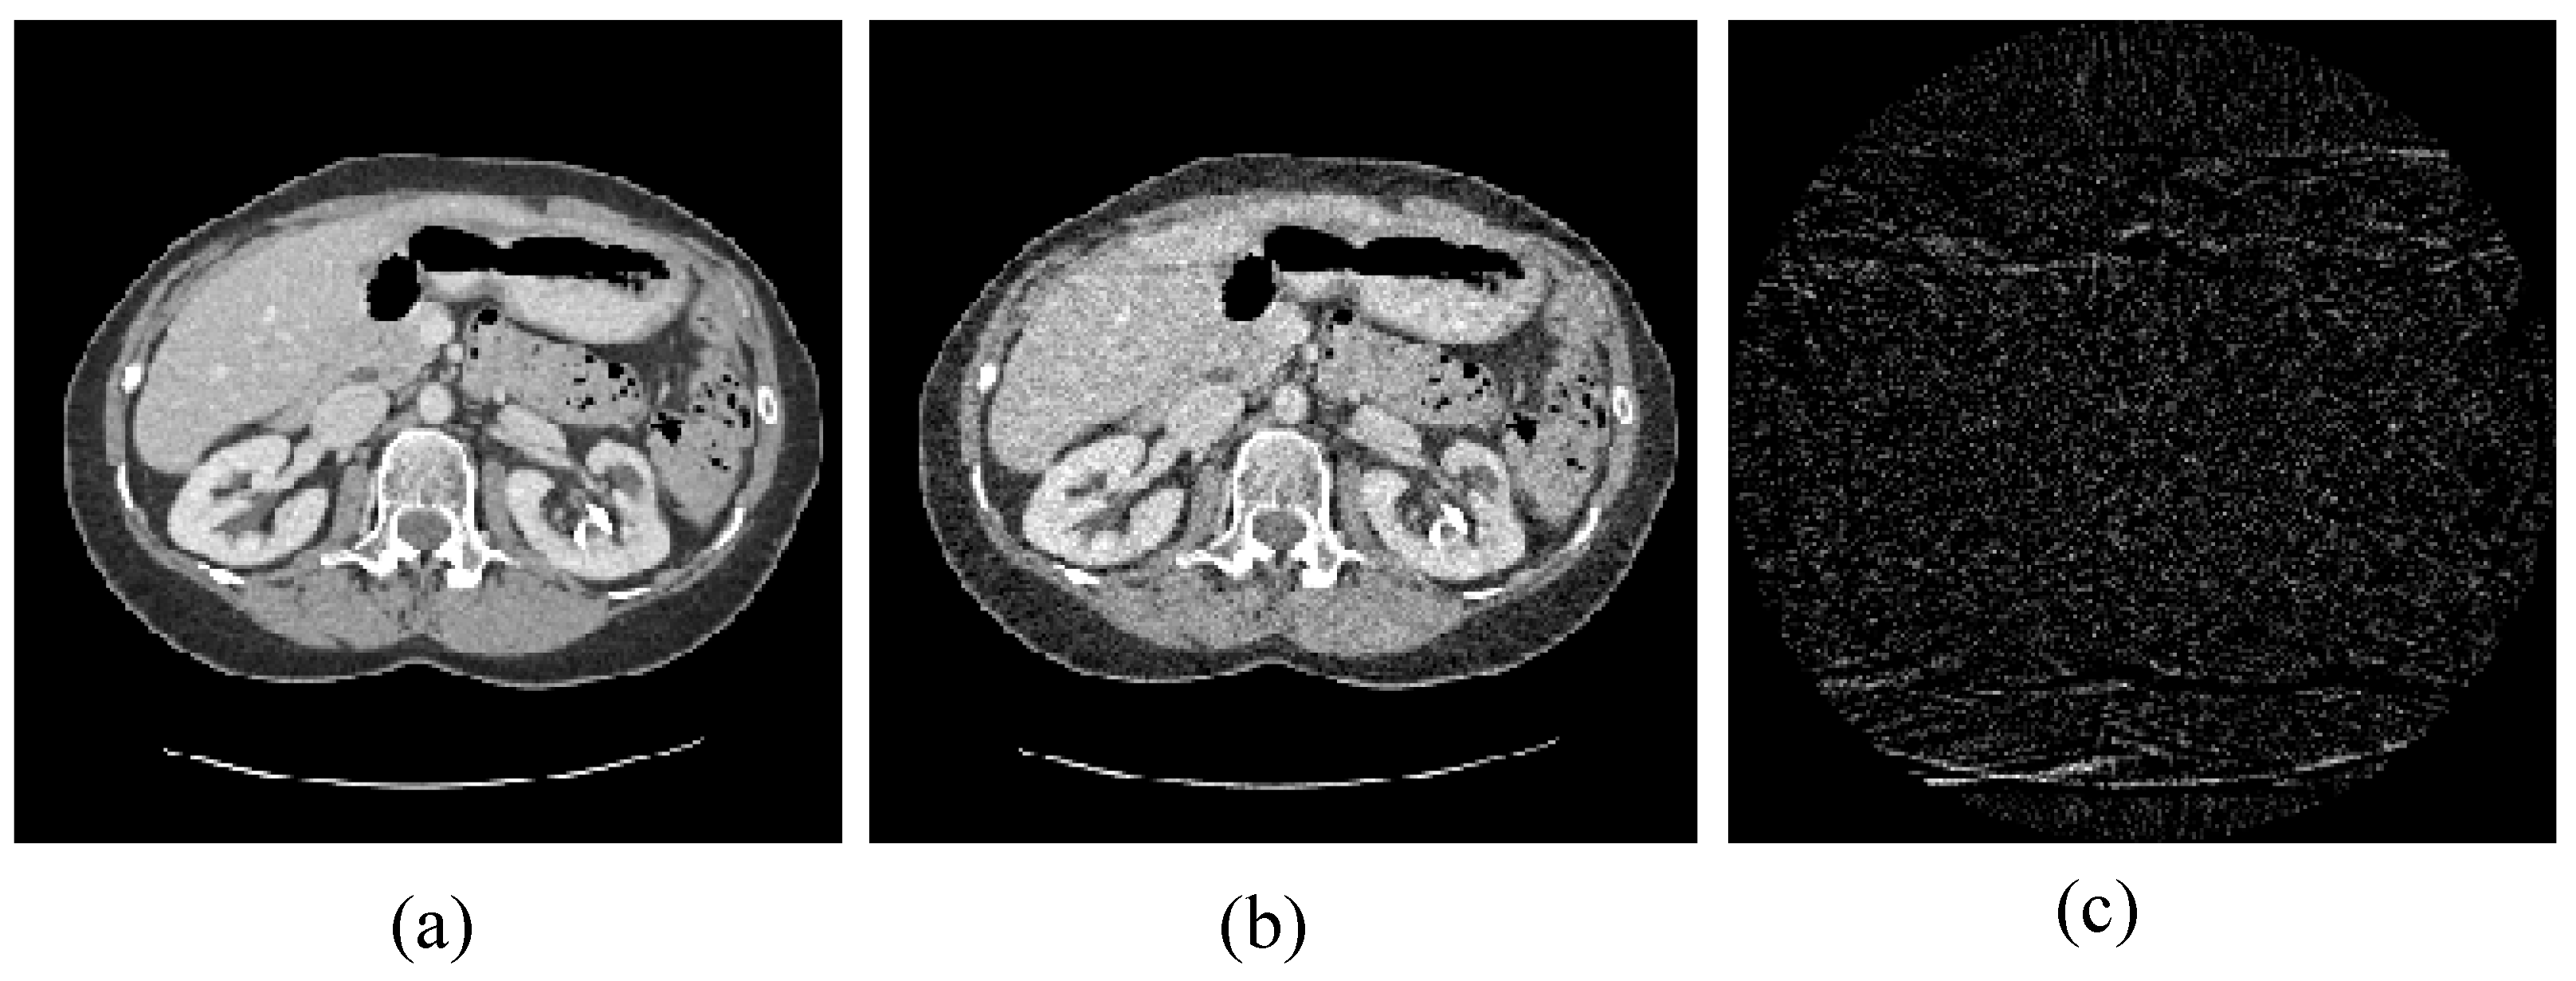

4.1. Image Reconstruction Experiment of Pelvic Image

The first image reconstruction experiment is using a pelvic image to show the feasibility of our algorithm for SVCT reconstruction, as shown in Figure 1. We extracted 80, 64, and 48 views from a full scan and selected parameters empirically. The parameters are set as follows: a = 0.5, γ1 = 0.3, and γ2 = 0.08. Figure 2, Figure 3 and Figure 4 show the ground truth and reconstruction images via FBP, OS-SART, TV, PICCS, TVPI-G, and our method NPICCS. From these figures, it is evident that our algorithm outperforms the other methods in terms of recovering image structures and suppressing noise. Specifically, the FBP and OS-SART results (as shown in Figure 2b,c, Figure 3b,c and Figure 4b,c) contain high levels of noise and artifacts, while TV results (as shown in Figure 2d, Figure 3d and Figure 4d) are characterized by blurring and staircasing effects. The PICCS and TVPI-G methods provide better results than the other approaches because of the introduction of prior information, but image edges are missing as shown in Figure 2e,f, Figure 3e,f and Figure 4e,f. At the same time, it can be seen that our method is able to preserve image edges and suppress noise effectively, as shown in Figure 2g, Figure 3g and Figure 4g.

Figure 1. Pelvic image for the experiments: (a) the target image; (b) the prior image; and (c) the difference image between the prior image and the target image.